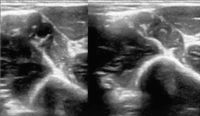

Kompressionssonographie

Abbildung 1: Kompressionssonographie: Armvene mit vollständig kollabierender Vena brachialis (rechts).